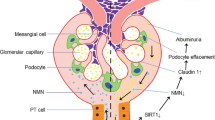

DKD is a common microvascular disease and one of the most serious chronic complications of diabetes [109]. With the increasing incidence of diabetes, DKD has become the main cause of ESRD [110]. The pathogenesis of DKD is complex. It is currently believed that genetic factors, hemodynamic changes, oxidative stress, inflammation, and mitochondrial damage jointly participate in the occurrence and development of DKD [111,112,113]. High glucose induces mitochondrial superoxide production in podocytes, further promoting mitochondrial dysfunction associated with mitochondrial morphological alterations and decreased mitochondrial membrane potential [114]. SIRT6 upregulation by plasmid transfection can protect mitochondrial function and alleviate oxidative stress by increasing AMPK phosphorylation, indicating that SIRT6 protects mitochondria and exerts antiapoptotic effects by activating the AMPK pathway [51]. Inflammation is also one of the main pathological features of DKD [115]. The mRNA levels of the inflammation-related factors IL-1β, IL-6, and TNF-α in podocytes were reduced by SIRT6. High glucose can activate the Notch signaling pathway in podocytes, and podocyte-specific overexpression of the intracellular domain of Notch1 (ICN1) induces proteinuria and glomerulosclerosis [116]. Activation of the Notch signaling pathway leads to endocytosis of nephrin and podocin, thereby destroying the structure of the podocyte split membrane and inducing proteinuria [117, 118]. SIRT6 protects against podocyte inflammation through epigenetic regulation of the Notch signaling pathway, suggesting that SIRT6 is a potential therapeutic target to protect podocytes from high glucose-induced injury. In brief, SIRT6 regulates the action of H3K9 deacetylation and binds to the promoter regions of Notch1 and Notch4 to inhibit transcription and activation of the downstream PTEN signaling pathway, further increasing autophagic flux and alleviating apoptosis and inflammation in podocytes [93]. In addition, SIRT6 protects podocytes against DKD by activating M2 macrophage transformation and acts as an immune regulator in inflammatory injury [119]. In addition, the NMN-producing enzyme nicotinamide phosphoribosyl-transferase (Nampt) has been proven to have a protective role in DKD. Proximal tubule Nampt-specific knockout mice showed SIRT6 downregulation, resulting in collagen deposition and a fibrotic phenotype, suggesting the protective role of Nampt-SIRT6 signaling in DKD [120]. This evidence shows that SIRT6 plays a protective role in high glucose-induced renal injury by reducing oxidative stress, mitochondrial damage, and inflammation, suggesting that SIRT6 could be a potential therapeutic target for preventing and delaying the progression of DKD.

Fibrosis is the common pathway associated with irreversible and progressive processes causing chronic development of kidney disease. TIF is mainly triggered by persistent chronic inflammation and fibrillary collagen accumulation. Increased proinflammatory cytokines interfere with intrarenal microcirculation and perfusion, contributing to EMT [181]. Activation of the inflammatory response-associated transcription factors NF-κB and STAT promotes tubulointerstitial inflammation and kidney fibrosis, and inhibiting these factors can ameliorate kidney fibrosis [182]. The TGF-β signaling pathway is the central mediator of renal fibrosis in progressive CKD. TGF-β promotes EMT and inhibits ECM degradation in renal tubular cells during the progression of CKD [183]. Wnt/β-catenin signaling regulates fibrosis and participates in the progression of CKD. β-Catenin overexpression in tubular cells induces epithelial dedifferentiation and EMT in mice [184]. The Notch signaling pathway also plays an important role in orchestrating the development of kidney disease. Notch expression in podocytes promotes glomerulosclerosis and albuminuria. Additionally, Notch expression in TECs promotes EMT-related snail1 and snail2 expression, thus contributing to TIF [185]. It is worth noting that the inflammatory response is also regulated by epigenetics. SIRT6 depletion induces chronic inflammation and fibrosis in the kidney and eventually leads to podocyte depletion, proteinuria, and the loss of kidney function. Studies have confirmed that SIRT6 negatively regulates the TGF-β and Wnt/β-catenin signaling pathways and plays an antifibrotic role [16]. In addition, high mobility group box 1 (HMGB1) exacerbates CKD progression by promoting vascular calcification. Bone marrow mesenchymal stem cell (BMSC)-derived exosomes downregulate HMGB1 expression through the SIRT6–HMGB1 pathway and ameliorate CKD-related fibrosis [17].